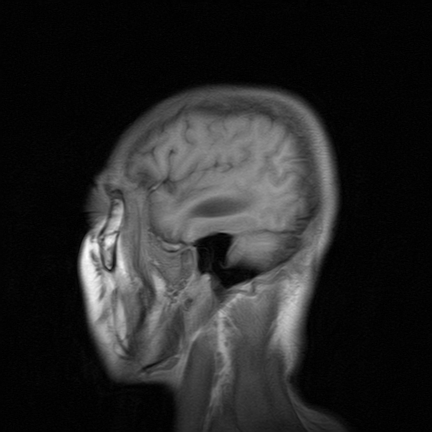

标题: MRI2064:少见病例。男性52,视力下降多年。 [打印本页]

标题: MRI2064:少见病例。男性52,视力下降多年。

四脑室区见混杂信号占位影,脑室系统扩张明显,临近结构显著受压称位,患者52岁,多考虑室管膜瘤可能性大

应该是来源于小脑蚓部的占位,如血管母细瘤或星形细胞瘤

小脑蚓部胶质脑膜瘤突入四脑室;肿瘤内见血管流空信号和钙化信号.

比较典型的脉络丛乳头状瘤并脑积水,鉴别小脑蚓部血管母细胞瘤。